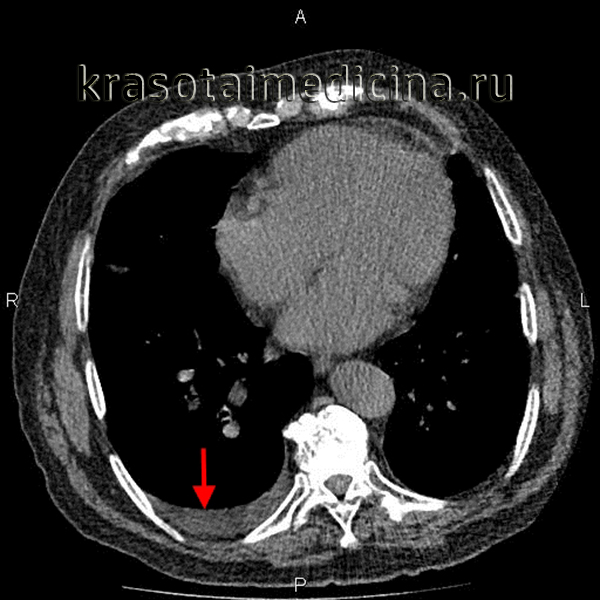

Эмпиема плевры на КТ выглядит как зона плотностью жидкости линзовидной или серповидной формы с четкими границами и с неоднородной структурой за счет участков мягкотканной плотности (фибрин) и плотностью газа. Газ может выявляться как в виде скопления над горизонтальным уровнем жидкости, так и в виде мелких пузырьков. Однако необходимо помнить, что пузырьки газа могут быть не только при эмпиеме плевры, но и без нагноения экссудата, вследствие предшествующих пункций плевральной полости или ее дренирования.